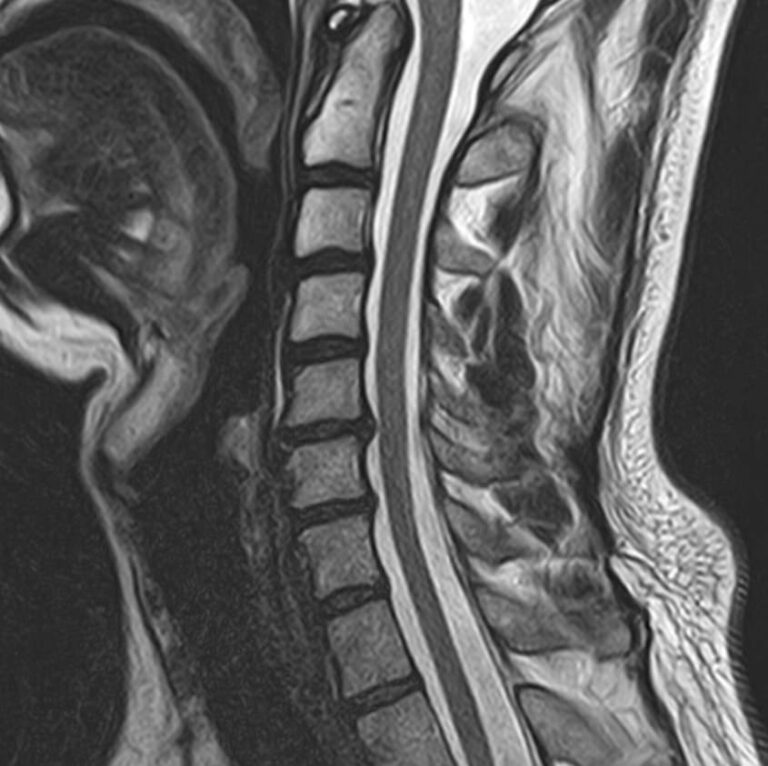

Магнитно-резонансная томография является современным, высокоточным, неинвазивным и безболезненным методом диагностики различной патологии позвоночного столба. Благодаря МРТ можно визуализировать костную структуру позвонков, оценивать состояние спинного мозга на исследуемом уровне, нервных корешков, связочного аппарата и окружающих мягких тканей. В основе метода лежит использование внешнего магнитного поля, которое не оказывает негативного влияния на организм человека. Отсутствие использования ионизирующего излучения делает МРТ безопасным методом исследования и позволяет проводить его достаточно часто по мере необходимости.

Комплексное обследование двух отделов позвоночника обычно проводится в тех случаях, когда имеется подозрение на множественное поражение различных отделов позвоночного столба, которые могут быть обусловлены развитием опухоли, метастатическим поражением, воспалительными или дегенеративными заболеваниями.